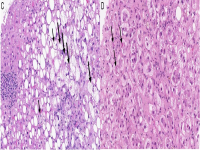

王功伟老师肾脏肿瘤系列讲座(二十九)一个好汉三个帮:嫌色细胞肾细胞癌病理诊断基础